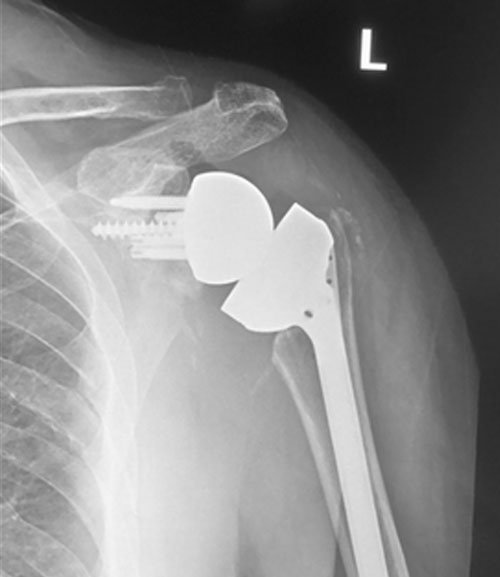

Shoulder after reverse replacement surgery

Shoulder before reverse replacement surgery

Move the slider to compare cuff tear arthropathy and superior migration of humeral head with left reverse total shoulder replacement